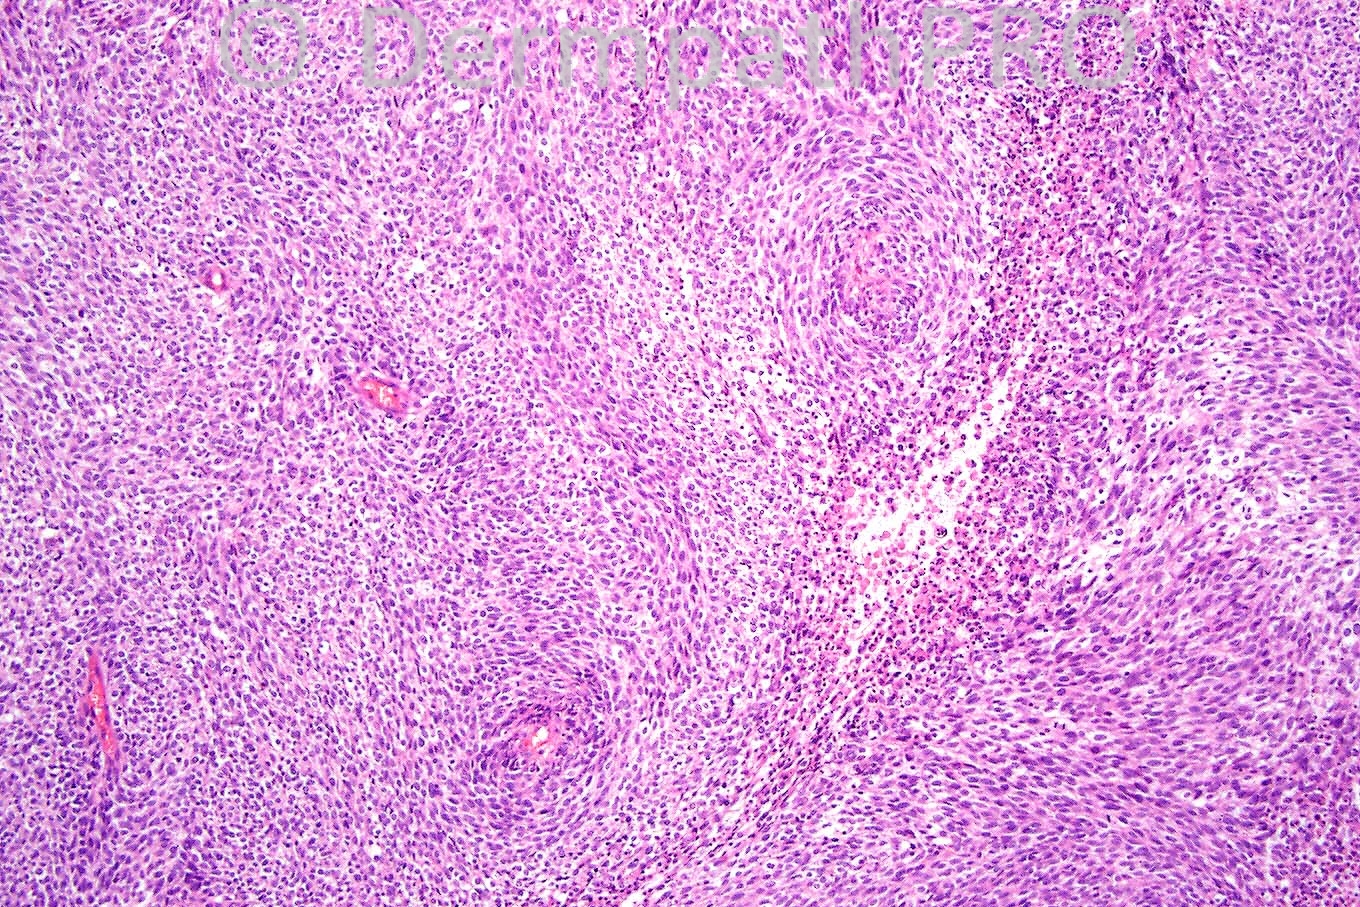

Male 37 years, tumor on leg.

This is a difficult case and synovial sarcoma is a good differential diagnosis. Although immunohistochemistry is necessary to extablish a final diagnosis, the perivascular accentuation as present in Figure 4 is very suggestive of a malignant peripheral nerve sheath tumor. I completely agree that melanoma would also have to be excluded. The final diagnosis was MPNST. I cannot remember whether the patient suffered from neurofibromatosis or not. Have a wonderful weekend.